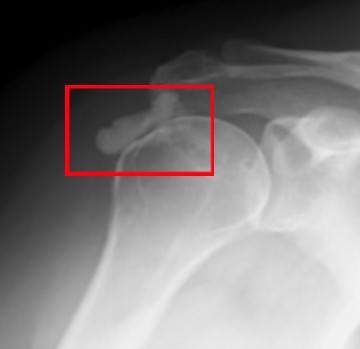

어깨 부위와 오른쪽 팔 상단 쪽을 엑스레이 촬영을 하고 그 부분을 함께 보여주셨습니다. 엑스레이에는 어깨 부위에 뿌옇게 뭔가 보였는데 그게 석회라고 하셨습니다. 석회 덩어리가 커져서 어깨를 회전할 때마다 근육을 찔러 통증을 유발한다고 말씀하셨습니다.

일반적으로 뼈에서는 석회가 원래 나오고 나왔던 석회가 다시 뼈로 흡수되는 과정이 반복되는데 그 과정 중에 석회가 남고 흡수가 잘 안 될 경우 석회가 뭉쳐서 통증을 유발한다고 합니다. 사실 이렇게 뭉친 석회는 쉽게 흡수가 이루어지지 않지만 결국 아주 오랜 시간이 지나면 자연 흡수도 가능하다고 합니다. 다만 그동안 발생하는 통증이 문제인 것입니다.

첫 엑스레이에서 덩어리로 보이던 석회는 작은 조각으로 바뀌어 있었습니다. 의사 선생님께서는 여기서 체외 충격파를 해도 더 이상 사이즈가 줄어들 것 같지도 않고 조각이 충분히 작아졌으니까 이대로 자연스럽게 뼈로 흡수될 것이라고 알려 주셨습니다.